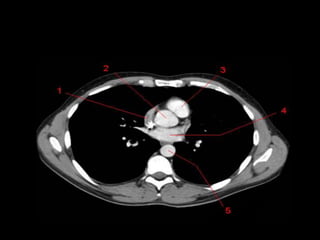

TC mediastino superior